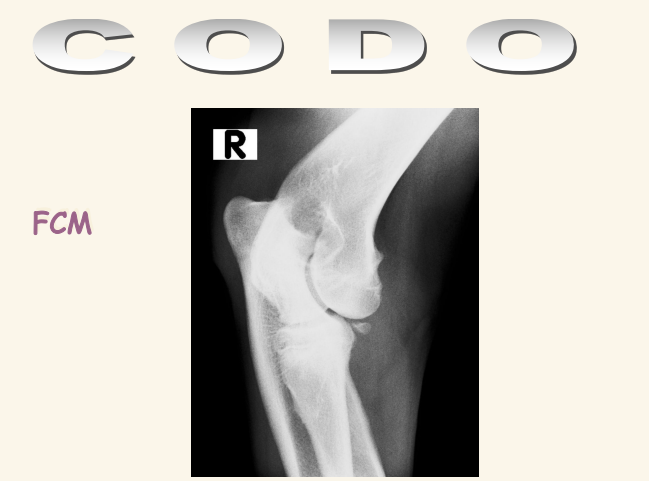

Codo

El condilo medial es mas fuerte que el lateral. Se dan fracciones en T o en Y. Luxacicones son mas dificiles que en codo

Existe la displasia del codo

- FCM: Fragmentación del Coronoides Medial, una de las lesiones típicas de displasia de codo

- NUPA: No Unión del Proceso Anconeo

- OCD: Osteocondritis disecante del condilo medial

- Incongruencia, mala articulacion de los 3 huesos.

- Se suele ver esclerosis subcondral que es la presencia de distinta densidad en el hueso bajo la articulación